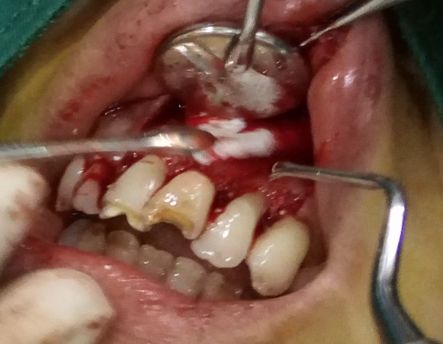

趙幫樹病例

來源于江思玉2群收集整理